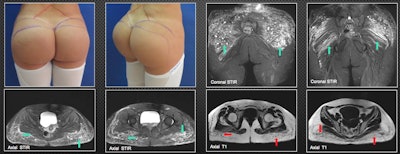

A 29-year-old patient was injected with biopolymers in the gluteal region six years ago to increase volume. She is currently asymptomatic, but she decided to schedule surgical removal of the material. MRI shows multiple nodular and other elongated lesions in the subcutaneous cellular tissue of the gluteal region. They are hypointense on T1-weighted images (red arrows) and hyperintense on T2-weighted and short-tau inversion recovery images (green arrows). This is compatible with biopolymers, which also compromise the maximum gluteal muscles bilaterally, especially on the left side; the other muscle groups in the pelvis show no infiltration by biopolymers. All figures courtesy of Dr. John J. Echeverri and RSNA 2020.Awareness of iatrogenic allogenosis, or foreign modeling agent reaction, must increase because it has a high socioeconomic impact and is not covered well in the literature, Echeverri and colleagues explained in an RSNA 2020 e-poster for which they received a certificate of merit. Get to know the multiple early and late complications and the different imaging modalities used in assessment of patients, they recommended.